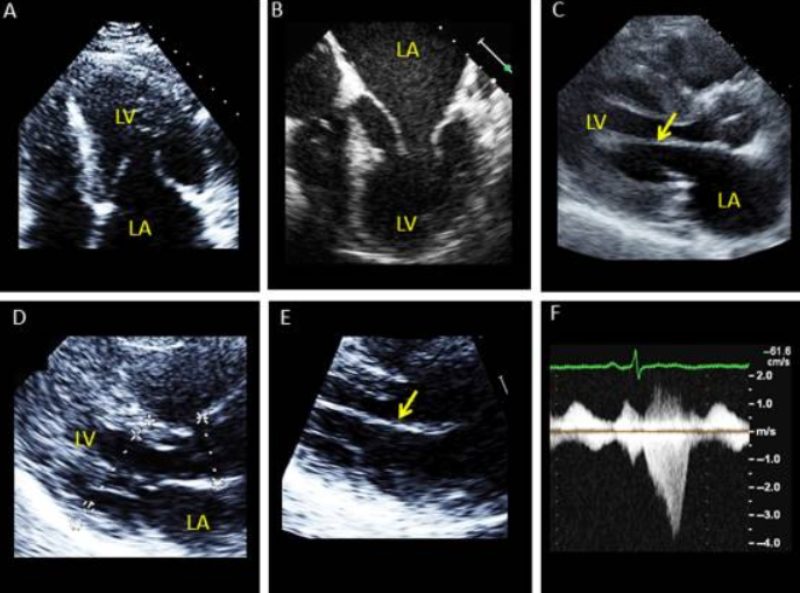

Hình ảnh siêu âm là một dữ liệu quan trọng trong việc chẩn đoán bệnh cơ tim phì đại và nhiều vấn đề tim mạch khác. Dưới đây là một số hình ảnh siêu âm thực tế.